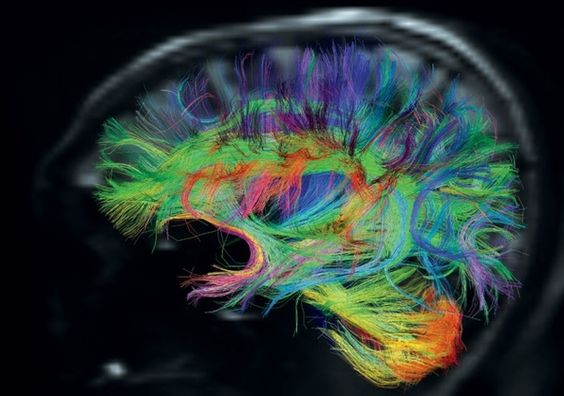

Одним из современных методов, позволяющих оценить микроструктурную организацию корковых трактов, является диффузионная тензорная МРТ (DTI –diffusion–tensor imaging) с трактографией. Данный метод основан на измерении величины и направления диффузии молекул воды в белом веществе мозга. Он позволяет провести трехмерную реконструкцию волокон белого вещества, оценить повреждение проводящих путей, определить эпилептогенный очаг, установить зависимость неврологического дефицита от степени структурных повреждений мозга, а также определить степень миелинизации и, соответственно, зрелости белого вещества.

Диффузно-тензорная трактография (разновидность МР-томографии) проводится пациентам с детским церебральным параличом для обнаружения морфологических изменений:

- Кистозно-глиозные поражения мозга;

- Кисты с ликвором;

- Пороки спинного и головного мозга;

- Гидроцефалия (повышение внутричерепного давления);

- Атрофия мозговой структуры;

- Внутримозговая демиелинизация;

- Артериовенозные мальформации (аномальные сочленения между венами и артериями).